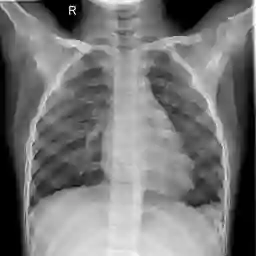

Large numbers of labeled medical images are essential for the accurate detection of anomalies, but manual annotation is labor-intensive and time-consuming. Self-supervised learning (SSL) is a training method to learn data-specific features without manual annotation. Several SSL-based models have been employed in medical image anomaly detection. These SSL methods effectively learn representations in several field-specific images, such as natural and industrial product images. However, owing to the requirement of medical expertise, typical SSL-based models are inefficient in medical image anomaly detection. We present an SSL-based model that enables anatomical structure-based unsupervised anomaly detection (UAD). The model employs the anatomy-aware pasting (AnatPaste) augmentation tool. AnatPaste employs a threshold-based lung segmentation pretext task to create anomalies in normal chest radiographs, which are used for model pretraining. These anomalies are similar to real anomalies and help the model recognize them. We evaluate our model on three opensource chest radiograph datasets. Our model exhibit area under curves (AUC) of 92.1%, 78.7%, and 81.9%, which are the highest among existing UAD models. This is the first SSL model to employ anatomical information as a pretext task. AnatPaste can be applied in various deep learning models and downstream tasks. It can be employed for other modalities by fixing appropriate segmentation. Our code is publicly available at: https://github.com/jun-sato/AnatPaste.